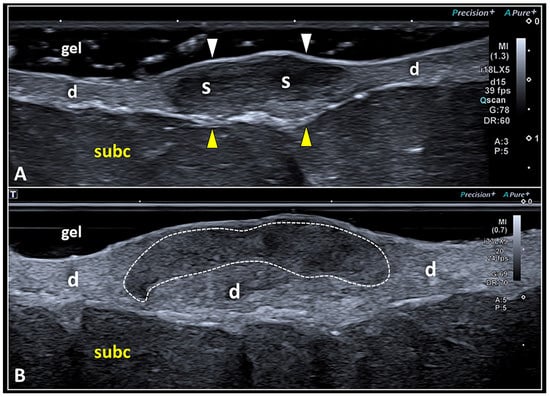

The dermis is a ribbon-like band less echogenic than the overlying epidermis and more echogenic than the underlying subcutaneous tissue [26,28]. Its echotexture is mainly related to the presence of (type I and III) collagen fibers and abundant ground substance that is highly hydrated [26,28]. Indeed, the latter is rich in water-binding molecules such as glycosaminoglycans and mucopolysaccharides [12,13]. The most common sonographic aspect of the skin scar is a focal hypoechogenicity of the dermis due to the presence of scarring tissue (Figure 5).

Figure 5.

High-frequency US imaging of SSs. Hypoechoic scarring tissue (S) may involve the dermis (d) in its entire thickness, displacing the overlying epidermis (white arrowheads) and the underlying dermo-hypodermal interface (yellow arrowheads) (A). Using the very high-frequency transducer, a scar (white dotted line) selectively involving the most superficial portion of the dermis (d) and preserving its deep component can be visualized using the suspension technique (B). subc: subcutaneous tissue.

As previously mentioned, despite the high concentration of collagen fibers inside the scar that generate additional acoustic interfaces compared with the physiological dermis, it is paradoxically hypoechoic [7]. This unexpected sonographic texture seems to be related to the presence of water molecules bound to the glycosaminoglycans and proteoglycans, and the fluids widely distributed inside the extracellular matrix of skin scars [7,32,33]. Nowadays, high-frequency US transducers allow a very detailed evaluation of the spatial location of the skin scar within the dermis [34]. Indeed, the fibrotic tissue can involve the entire thickness of the dermal layer or can selectively involve its superficial or deep portion (Figure 5).